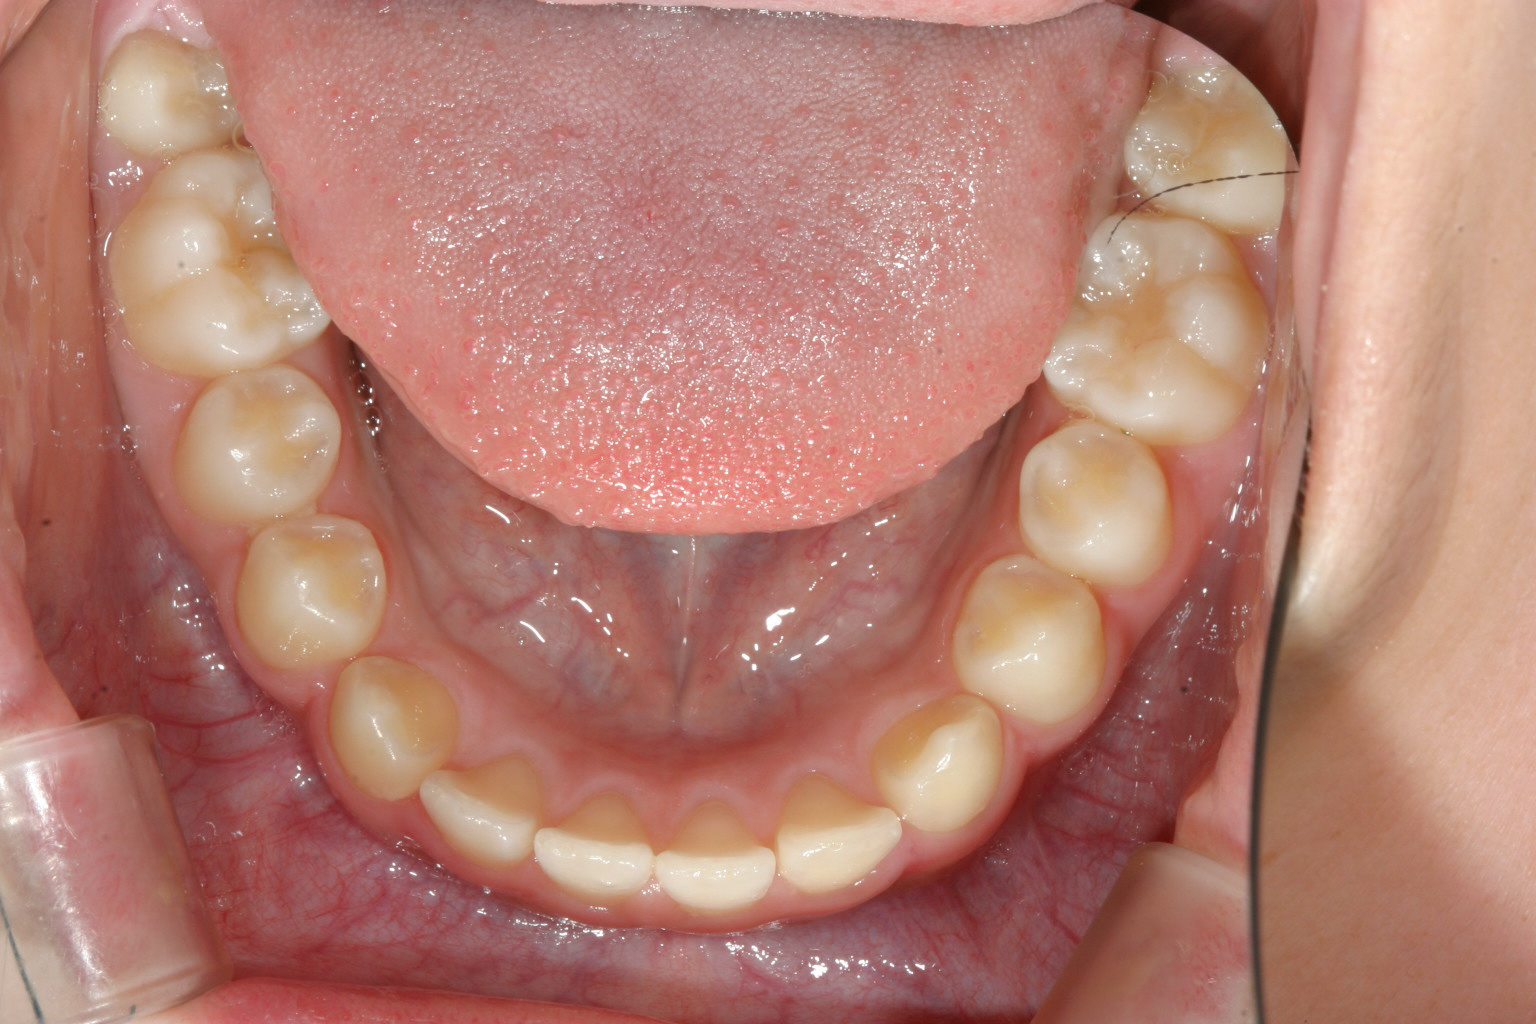

下顎は綺麗なアーチですね~

うけ口になってます。